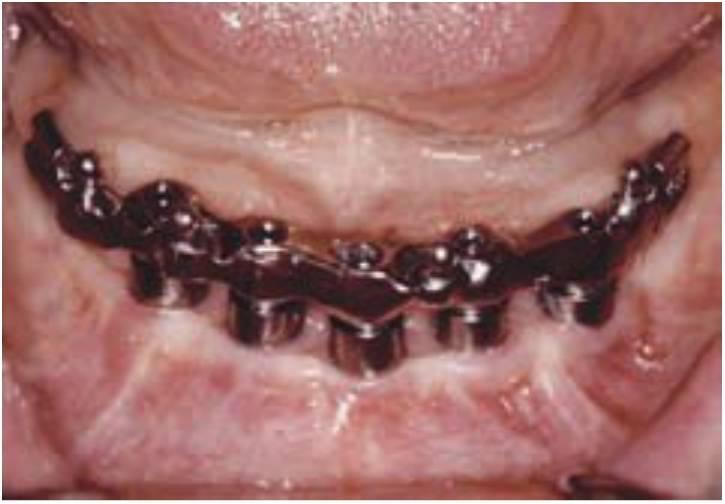

Una razón primaria para considerar los implantes dentales para sustituir los dientes perdidos es el mantenimiento del hueso alveolar (fig. 1-26). El implante dental colocado dentro del hueso sirve a la vez de anclaje para el aparato prostético y como uno de los mejores procedimientos de mantenimiento preventivo en odontología. Se puede aplicar tensión y presión al hueso circundante al implante. como resultado, se invierte la disminución en la trabeculación del hueso que aparece después de una extracción dentaria. Hay un aumento de las trabéculas óseas y en la densidad cuando se inserta el implante y empieza a funcionar. El volumen óseo total también se mantiene con un implante dental.

Incluso los injertos óseos de cresta ilíaca en las mandíbulas, que suelen ser reabsorbidos durante los 5 siguientes años cuando no hay inserción de implante, son estimulados y mantienen el volumen óseo total y la integración del implante. Un implante endoóseo puede mantener el ancho y alto del hueso mientras que el implante se mantenga en buena salud. Al igual que para un diente, la pérdida de hueso periimplantario puede medirse en décimas de milímetro y puede representar más de la veinteava parte de la estructura pérdida, en comparación con la reabsorción que se produce con las prótesis removibles.

La estabilidad y la retención de la prótesis implantosoportada son las grandes mejorías obtenidas en comparación con las dentaduras mucosoportadas (fig. 1-32). Los resultados mecánicos de la retención implantológica son muy superiores a los de la retención sobre tejido blando proporcionada por las dentaduras o los adhesivos y causan menos problemas asociados. El soporte implantológico de la prótesis final es variable, dependiendo del núm ero y posición final de los implantes; aunque todas las opciones de tratamiento han demostrado mejorías significativas.